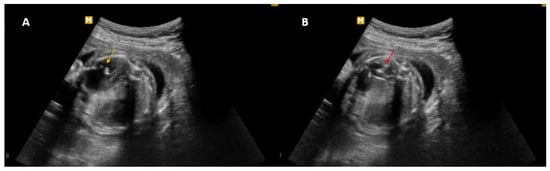

Nevertheless, in cases of prenatal thoracic anomalies associated with hydrops, with large or rapidly growing lesions, thoracoamniotic shunting has been shown to markedly enhance perinatal survival rates [21]. The effectiveness of thoracoamniotic shunting in draining dominant macrocysts in complex subtype I CCAM has been consistently highlighted in various cohort studies and case reports [22,23]. Wilson et al. [22] performed a retrospective analysis to assess thoracoamniotic shunt placement as a treatment option for primary pleural effusion or macrocystic CCAM in fetuses presenting with hydrops or a high risk of pulmonary hypoplasia. In cases of hydrops prior to shunting, in utero shunt therapy resolved hydrops in 7 out of 9 fetuses (78%). Perinatal mortality rates were 33% in the pleural effusion group and 30% in the CCAM group. The study found no significant differences in gestational age at the time of shunting or in CCAM volume and lesion laterality between survivors and non-survivors. However, a clinically significant reduction in CCAM mass volume and CVR was observed following shunting [22] (Figure 5).

Figure 5. Two-dimensional ultrasonography. Thoracoamniotic shunting placement in a case of congenital adenomatoid cystic malformation subtype I. (A) Catheter penetration inside the cyst (yellow arrow). (B) Placement of the thoracoamniotic shunting (red arrow). Source: the authors.